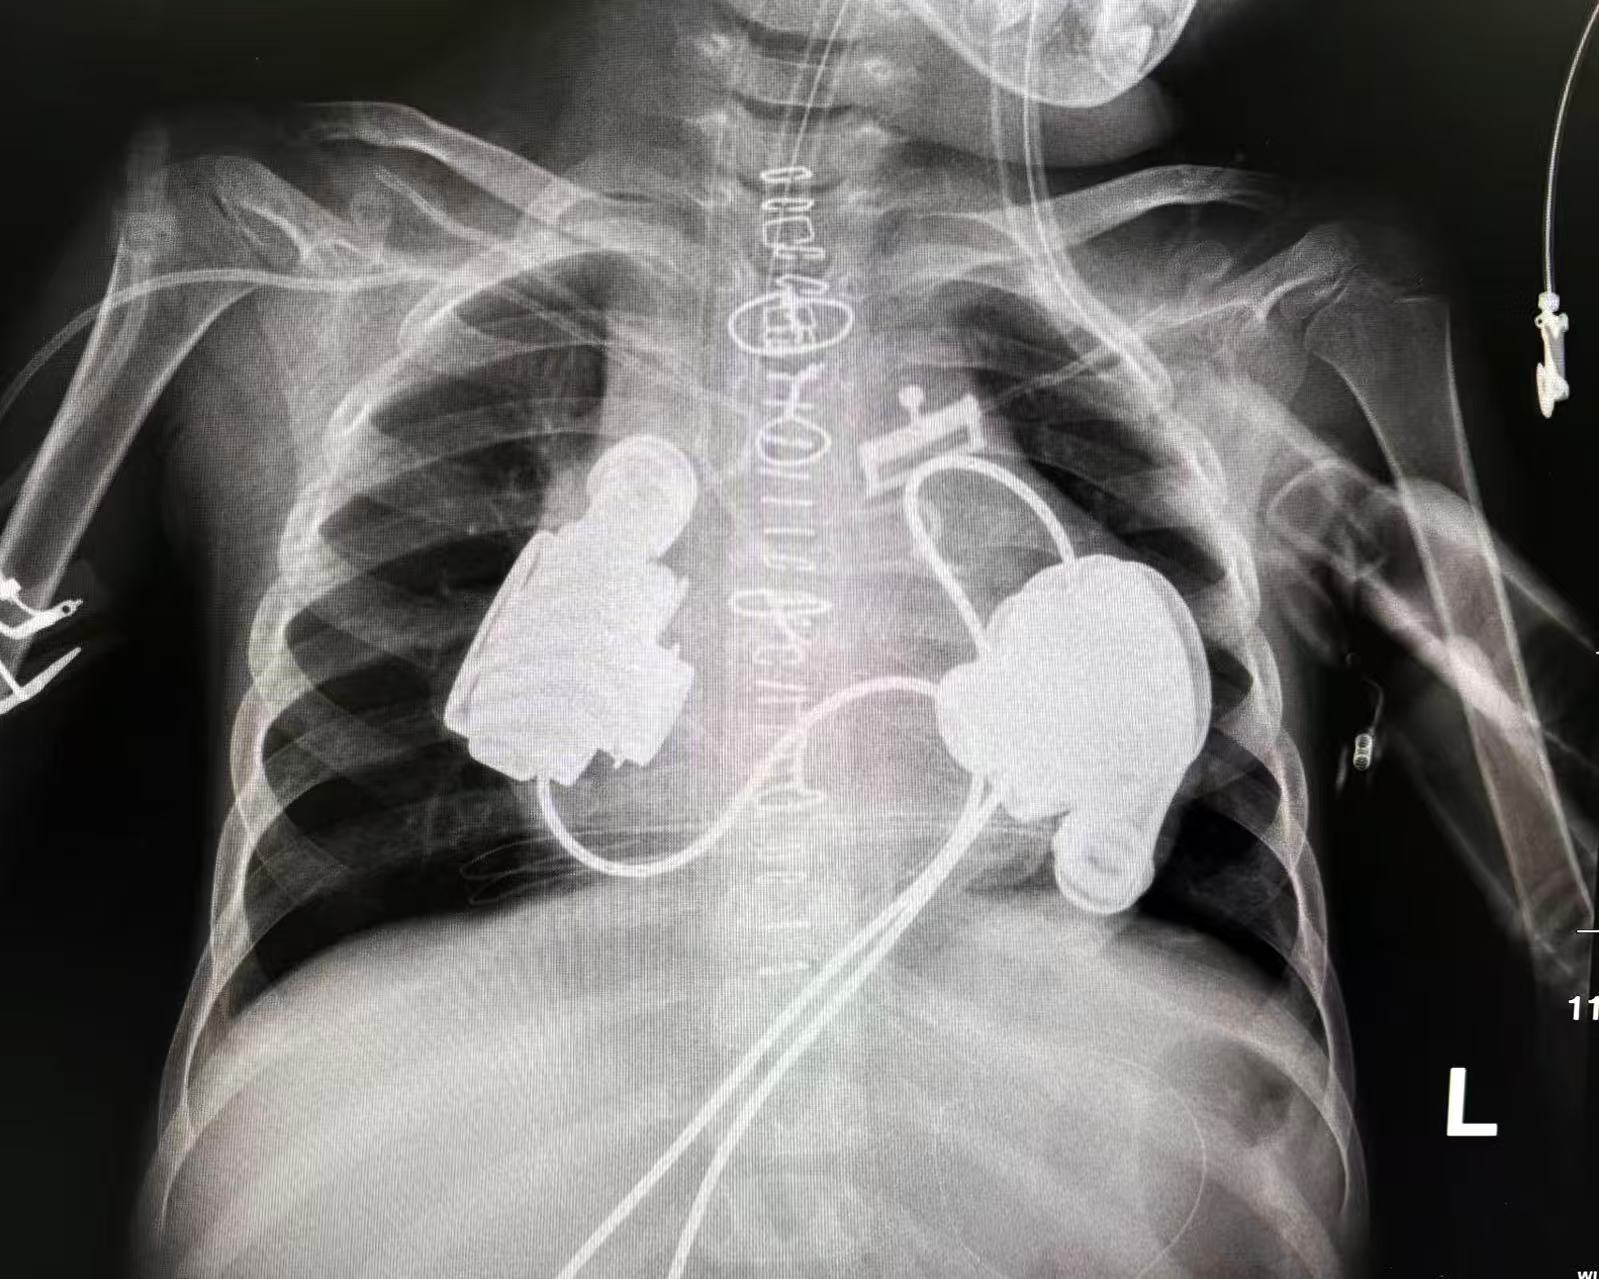

▲双人工心脏植入手术后胸片

8月20日,刘晓程教授主刀与南京市儿童医院莫绪明教授团队联合开展手术。在精密的术前规划与术中配合下,两颗定制“火箭心”成功植入小妮的左心室和右心房,手术全程顺利。术后监测显示,小妮的心肺功能迅速得到支撑,生命体征逐步稳定。她就此成为全球接受双人工心脏植入手术的最低体重限制型心肌病儿童,刷新了该领域的世界纪录。